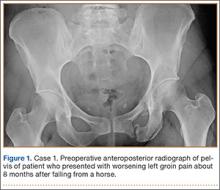

A 45-year-old woman fell from a horse about 8 months before presenting to the orthopedic outpatient clinic. Pelvic radiographs obtained after the fall were negative for fracture, but subsequent pelvic magnetic resonance imaging led to the diagnoses of minimally displaced left superior and inferior pubic ramus fractures and associated right-sided sacral ala fracture. The patient was treated with protected weight-bearing according to symptoms, but increasing activity-related pain and discomfort in the left groin persisted for months after injury. These symptoms were treated with analgesic medication, physical therapy, and chiropractic manipulation. Repeat imaging showed hypertrophic nonunions of the left superior and inferior pubic rami (Figure 1). Findings of the serologic testing performed for infection and metabolic deficiencies were normal at that time. The patient was referred for surgical consultation.

Pelvic CT showed the nonunion site and the osteology of the inferior and superior pubic ramus of the pelvis, as well as minimal displacement and good alignment of the rami.